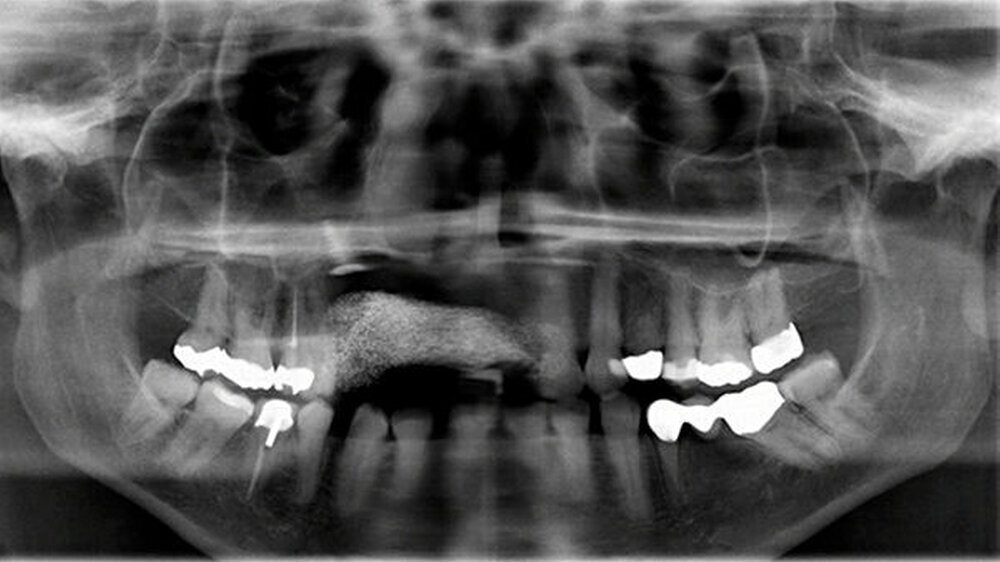

Zudem wurde eine postoperative Röntgenkontrolle mittels OPG durchgeführt (Abbildung 7). Bei optimaler Mundhygiene war der Heilungsverlauf stadiengerecht, ohne dass Dehiszensen oder eine Infektion aufgetreten wären.